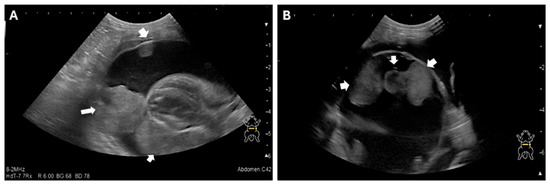

Veterinary cardiology has become a permanent fixture, both in the way of services provided by general practitioners, and also in specialized centers, which are being established in growing numbers around the world. Acquired heart disease, which develops and progresses with age, accounts for the vast majority of cardiac cases. They are also the subject of greatest interest to researchers, due to the prevalence and difficulties encountered during their treatment. Among them, the most common are myxomatous mitral valve disease in small-breed dogs, dilated cardiomyopathy in large-breed dogs and hypertrophic cardiomyopathy in cats. In contrast, congenital heart defects, which are significantly less common, can pose considerable diagnostic challenges and be cumbersome in terms of selecting the optimal treatment protocol. Due to the rapidly developing branch of interventional cardiology, including minimally invasive procedures, a growing number of defects, such as patent ductus arteriosus, pulmonic stenosis, atrial septal defects or ventricular septal defects, can be successfully addressed by surgical methods. In many cases, such treatment results in a complete recovery, which positively affects the rest of the animal's life. With the use of advanced diagnostics, such as 3D and 4D transesophageal echocardiography, cardiac magnetic resonance imaging (MRI), and cardiac computed tomography (CT), the characteristics of acquired and congenital defects and their complexities can be assessed very accurately, favoring the selection of optimal treatment methods, as well as allowing the determination of possible strategies for surgery. Thanks to this comprehensive approach, veterinary cardiology services in many countries around the world have achieved incredibly high standards of care.